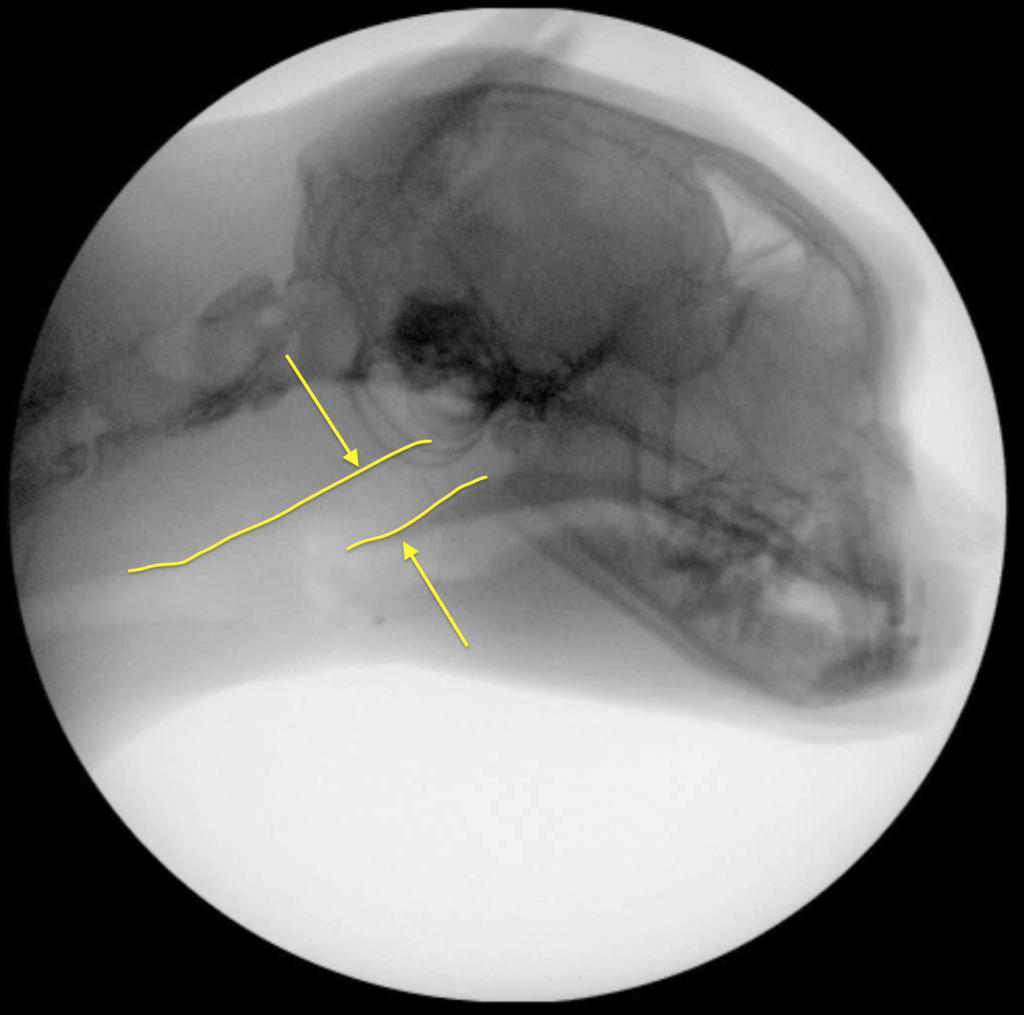

Коллапс обычно происходит во время вдоха, следовательно, это не длительное, а динамическое отклонение. Динамический назофарингеальный коллапс может быть как первичной, так и вторичной патологией5. У людей ДНФК был признан основной причиной синдрома обструктивного апноэ во сне (англ. obstructive sleep apnea syndrome; OSAS), однако в ветеринарии мелких домашних животных это состояние описывается редко, особенно у кошек5. Несмотря на сходные механизмы обструкции носоглотки у людей, собак и кошек, динамический коллапс у людей преимущественно проявляется во время сна7,8 в отличие от кошек и собак, у которых наиболее выраженные приступы одышки наблюдаются во время физической нагрузки или стресса1,2,3,5. Возможно, попытки экстраполировать методы лечения данной патологии из медицины человека являются ошибочными8.Золотым стандартом для подтверждения диагноза «динамический назофарингеальный коллапс у кошек» является рентгеноскопия акта дыхания1,2,5.

Рентгеноскопия акта дыхания проводится без седации, в естественном сидячем или стоячем положении животного.

У одного пациента коллапс проявлялся только на глубоком вдохе, у остальных трех кошек – на каждом вдохе (возможно, само исследование было стрессом для животных, что провоцировало их делать глубокие вдохи).